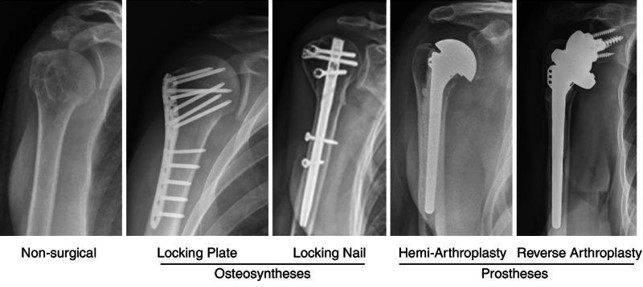

Questo obiettivo può essere raggiunto dal chirurgo grazie a diverse tipologie di mezzi di sintesi. Placche e viti associate eventualmente a tiranti possono essere la scelta nei giovani, mentre nella persona più in là con gli anni, chiodi endomidollari o protesi di spalla (link a futuro articolo sulla protesi di spalla) potrebbero essere la strategia migliore (8,10,11,12).

Immagine che illustra le principali soluzioni di intervento in esiti di frattura di spalla. Tratta da Orthogeriatrics: The Management of Older Patients with Fragility Fractures [Internet]. 2nd edition. Falaschi P, Marsh D, editors. Cham (CH): Springer; 2021.